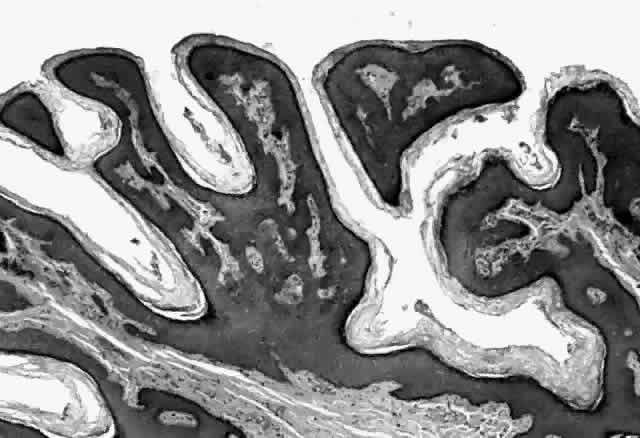

Molluscum contagiosum is a papule with lobular downgrowth of epithelium into the dermis and a central “crater” on the surface (Fig. 11). The epithelium and infected cells demonstrate hyperplasia. Basal cells divide more rapidly (6.1 day turnover decreasing to 3.4 days) and infected cells show more rapid migration through the epithelium as well as cessation of host DNA transcription.121,122 Each lobule demonstrates a progression from base to top. The malpighian cells contain eosinophilic elementary bodies (Fig. 12). These coalesce to form a hyaline molluscum body (HendersonPaterson body).123 The cytoplasmic molluscum bodies increase in size until they distort and displace the nucleus, sometimes becoming larger than the original host cell (Fig. 13). At the top of the lobule in the granular cell layer, the Henderson-Paterson inclusion body changes from eosinophilic to basophilic. When the overlying stratum corneum loses its integrity, the crater is formed (see Fig. 10). Microdissection revealed124 and scanning electron microscopy confirmed125 the presence of a sac surrounding the viral inclusion body within each cell, which has been speculated to provide an immunologically sheltered site for viral reproduction.

Fig. 11. Molluscum contagiosum, histology. Low-power view of lobular epithelial downgrowth and central umbilicated crater. (Original magnification × 50)

Fig. 12. Molluscum contagiosum, histology. Evolution of molluscum bodies from base (left) to center of lobule (right). (Original magnification × 200)